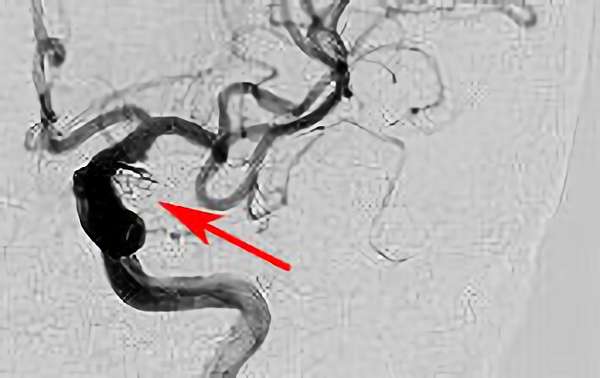

'26年4月

左後下小脳動脈瘤

80代

大阪府の病院

No.1631 手術中